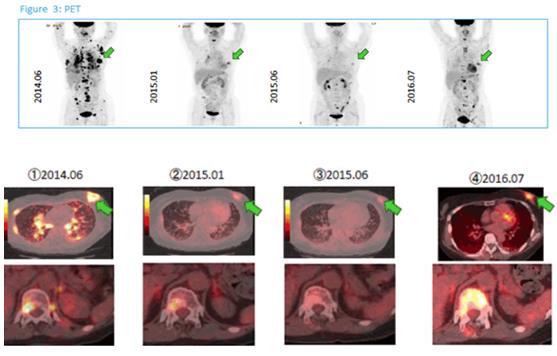

免疫治療:肺腺癌,男,72歲

穩定狀態:病情穩定,在一段時間內腫瘤組織既沒有增大也沒有縮小。背景介紹 -INTRODUCTION-在日... -